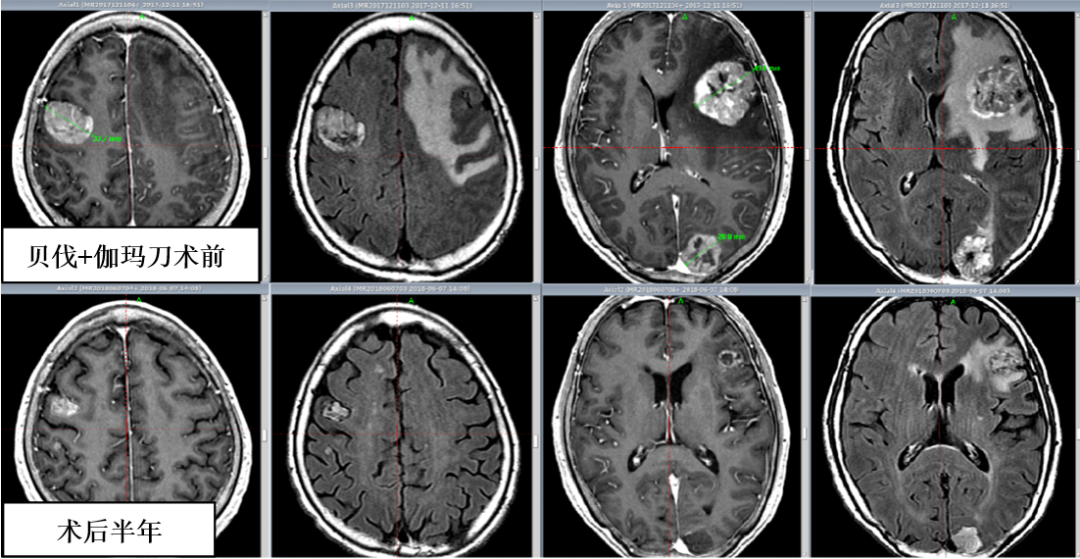

2、伽玛刀联合贝伐珠单抗治疗多发巨大脑转移瘤。经5年使用观察,该方法在提高病灶局控率、延长患者生存期的同时快速、显著降低了神经功能的损害,提高患者生存质量,为多发巨大脑转移瘤临床治疗的新思路。2019年神经外科分会肿瘤学组会议上我们分享此经验。